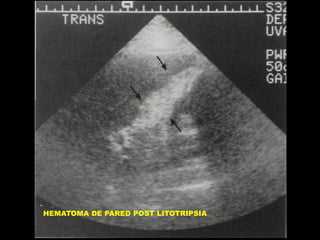

HEMATOMA

• TRAUMA ACCIDENTAL

• PUNCIONES

• DRENAJES

• LITOTRIPSIA EXTRACORPOREA

HEMATOMA DE PARED POST LITOTRIPSIA